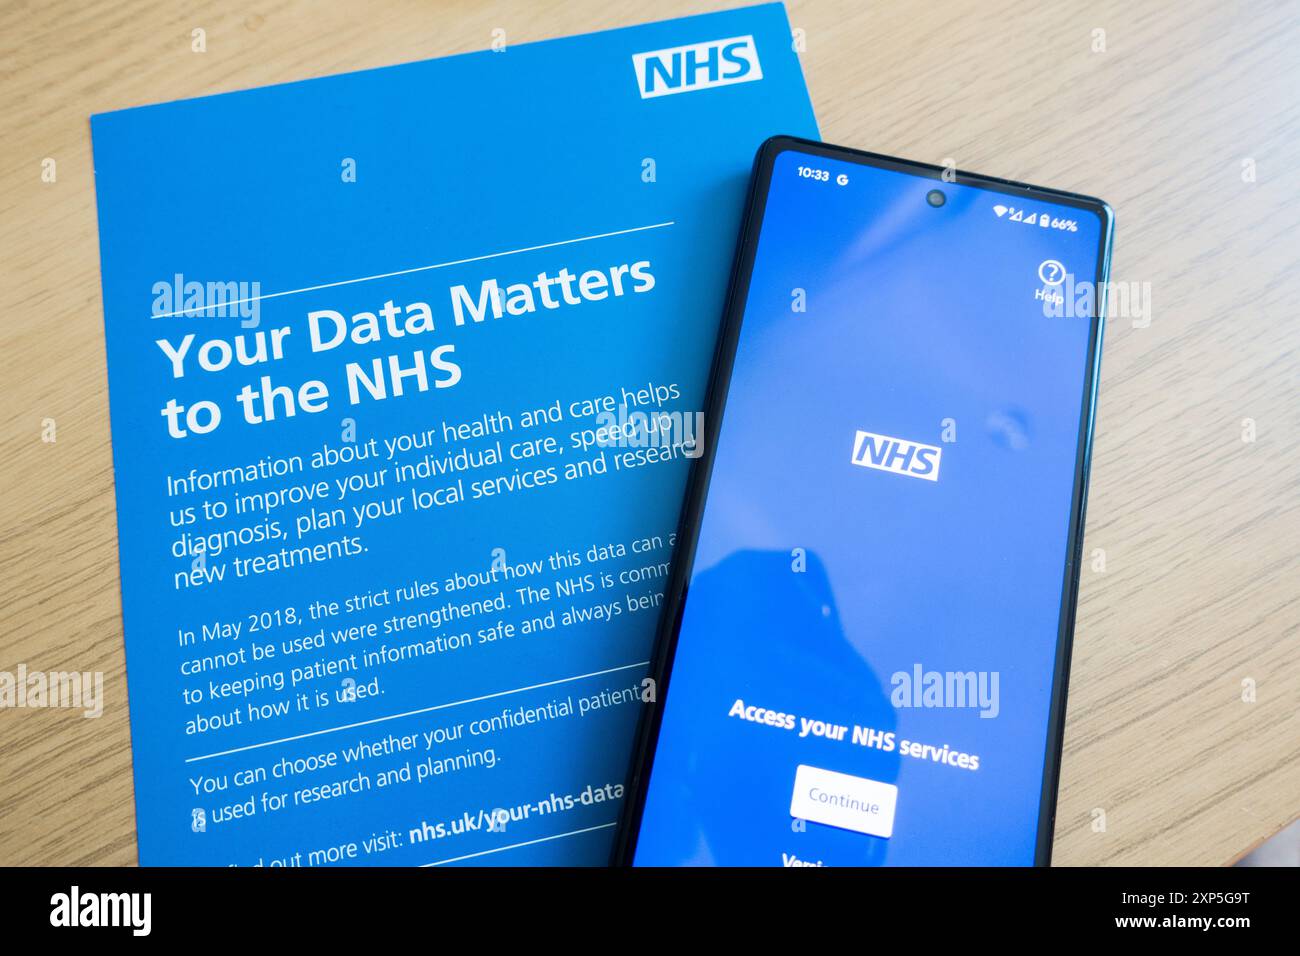

NHS data sharing Stock Photohttps://www.alamy.com/image-license-details/?v=1https://www.alamy.com/nhs-data-sharing-image616007892.html

NHS data sharing Stock Photohttps://www.alamy.com/image-license-details/?v=1https://www.alamy.com/nhs-data-sharing-image616007892.htmlRM2XP5G9T–NHS data sharing

NHS Data. Sharing data Stock Photohttps://www.alamy.com/image-license-details/?v=1https://www.alamy.com/nhs-data-sharing-data-image616007893.html

NHS Data. Sharing data Stock Photohttps://www.alamy.com/image-license-details/?v=1https://www.alamy.com/nhs-data-sharing-data-image616007893.htmlRM2XP5G9W–NHS Data. Sharing data

NHS Data. Sharing data Stock Photohttps://www.alamy.com/image-license-details/?v=1https://www.alamy.com/nhs-data-sharing-data-image616007875.html

NHS Data. Sharing data Stock Photohttps://www.alamy.com/image-license-details/?v=1https://www.alamy.com/nhs-data-sharing-data-image616007875.htmlRM2XP5G97–NHS Data. Sharing data